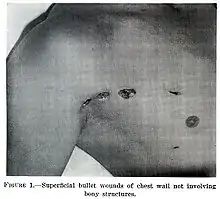

Chest

Most penetrating injuries are chest wounds and have a mortality rate (death rate) of under 10%.[14] Penetrating chest trauma can injure vital organs such as the heart and lungs and can interfere with breathing and circulation. Lung injuries that can be caused by penetrating trauma include pulmonary laceration (a cut or tear) pulmonary contusion (a bruise), hemothorax (an accumulation of blood in the chest cavity outside of the lung), pneumothorax (an accumulation of air in the chest cavity) and hemopneumothorax (accumulation of both blood and air). Sucking chest wounds and tension pneumothorax may result.